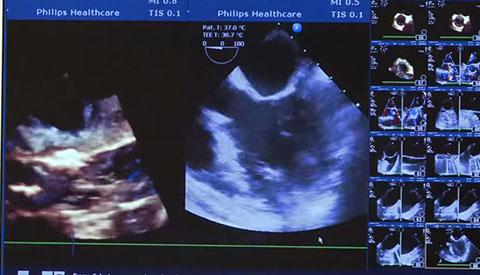

Uw patiënt is gediagnosticeerd met symptomatische aortastenose. Ze is 85 jaar, heeft diabetes en een hoge bloeddruk. U weet dat ze een verhoogd risico loopt en niet in aanmerking komt voor hartchirurgie, maar misschien wel voor transkatheter aortaklepvervanging (TAVR). Vandaag de dag bieden innovatieve beeldvormingsoplossingen en percutane instrumenten hoop voor sommige patiënten die tot nu toe geen andere opties hadden .

Meer informatie over onze cardiologieoplossingen.